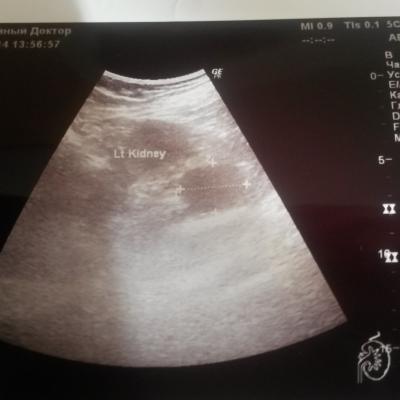

Здравствуйте, Мне 64 года на УЗИ брюшной полости в проекции левого надпочечника обнаружено гипоэхогенное образование 38 на 30 мм с четкими ровными контурами, однородной структуры. При ЦДК слабый смешанный кровоток. Размеры левой почки 120 на 58, контуры четкие, ровные, эхоструктура паренхимы однородная- 17 мм, ЧЛС центрально расположена. Я понимаю, что нужно делать КТ, но все таки, может по УЗИ тоже можно ответить, злокачественная ли это опухоль? Заранее спасибо.

Нет, по УЗИ чётко ответить нельзя. Надо делать МСКТ (мультиспиральную компьютерную томографию).